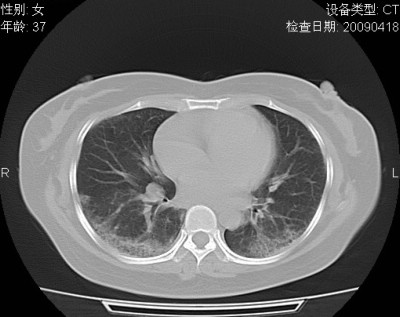

以下是引用随光逐影在2009-4-20 8:03:00的发言:[br]两肺间质性病变(间质性肺炎?特发性肺间质纤维化?)。

以下是引用51736011在2009-4-21 16:24:00的发言:[br]两肺间质性病变(间质性肺炎?特发性肺间质纤维化?)。